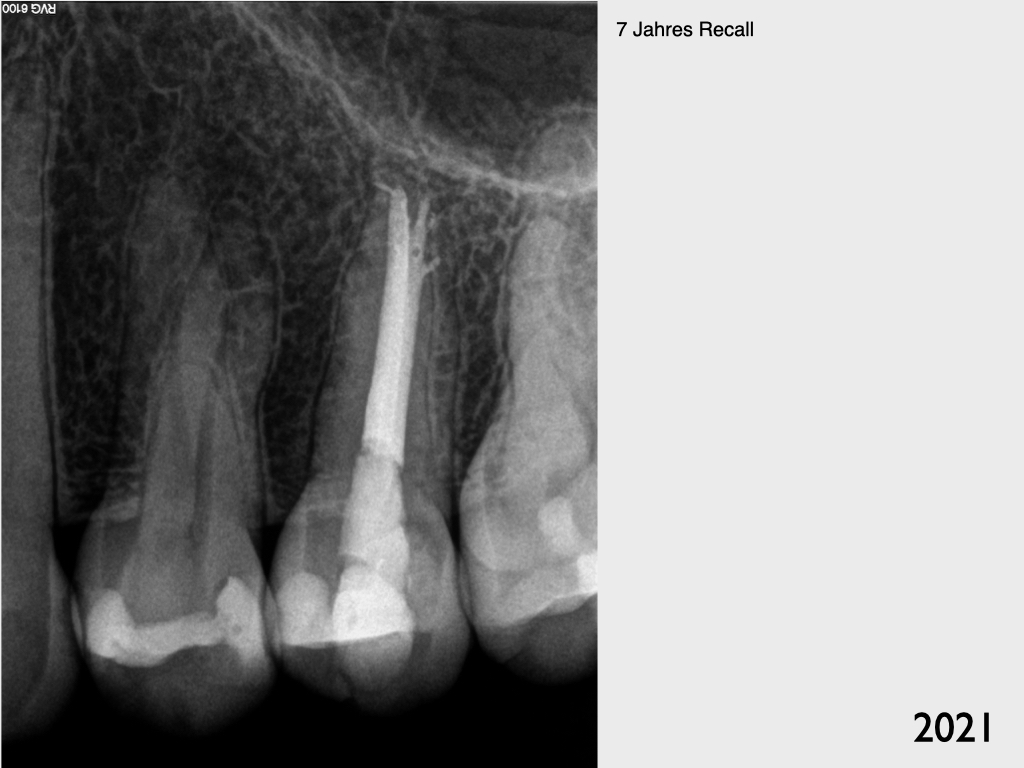

Recall 7 Jahre